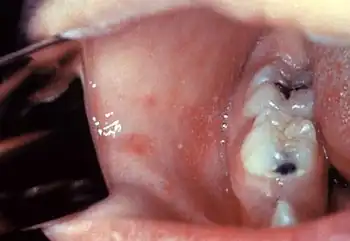

Photomicrograph of a lung tissue specimen, showing the histopathologic changes encountered in a case of measles pneumonia. Included in this view are numerous leukocytes and a multinucleated giant cell. Normal alveolar cytoarchitecture has been obliterated.[46]

46. ^ Ewing Jr EP (1972). "This photomicrograph of a lung tissue specimen, reveals the histopathologic changes encountered in a case of measles pneumonia. Included in this view, are numerous leukocytes, and a multinucleated giant cell. Normal alveolar cytoarchitecture has been obliterated". CDC, Public Health Image Library. U.S. Government. 859. Archived from the original on 10 December 2023. Retrieved 16 January 2024.